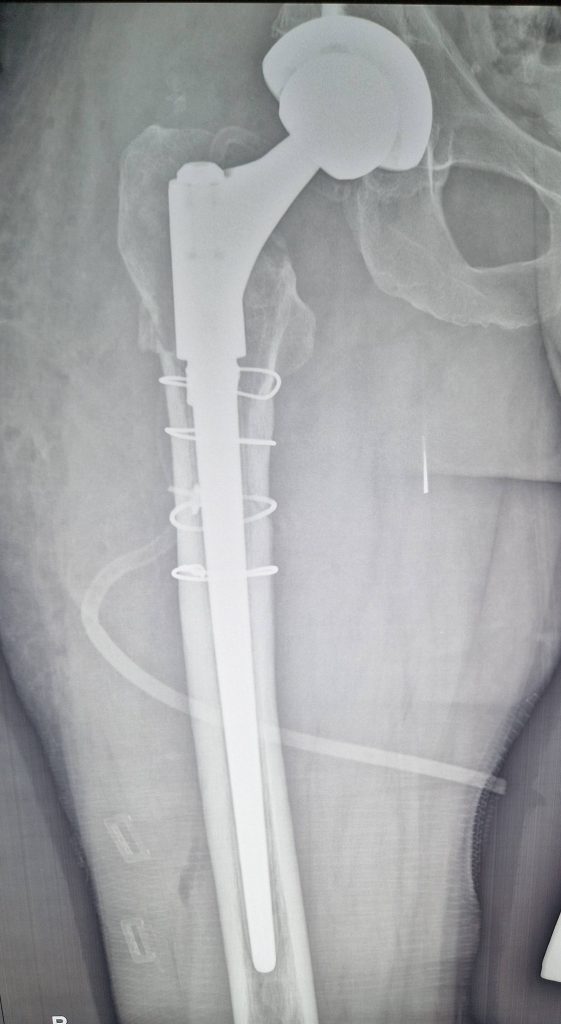

Ревізійне ендопротезування, при перипротезних переломах, особливо тип В2, потребує заміни ніжки протеза, як правило на ревізійну, і стабільного остеосинтеза відламків проксимального відділу стегнової кістки з заміщенням дефектів кістки трансплататом.

Клінічний приклад ревізійного ендопротезування при перипротезному переломі стегнової кістки представлено на рентгенограмах.

Ревізійне ендопротезування, при перипротезних переломах, особливо тип В2, потребує заміни ніжки протеза, як правило на ревізійну, і стабільного остеосинтеза відламків проксимального відділу стегнової кістки з заміщенням дефектів кістки трансплататом. Клінічний приклад ревізійного ендопротезування при перипротезному переломі стегнової кістки представлено на рентгенограмах.